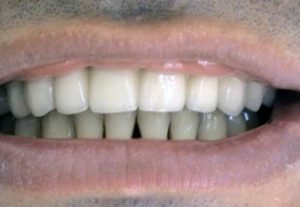

Implantation & prosthetics – „all in one“

1. PHASE - implant placement

2. PHASE - before taking prints

3. PHASE - temporal crown before final implant